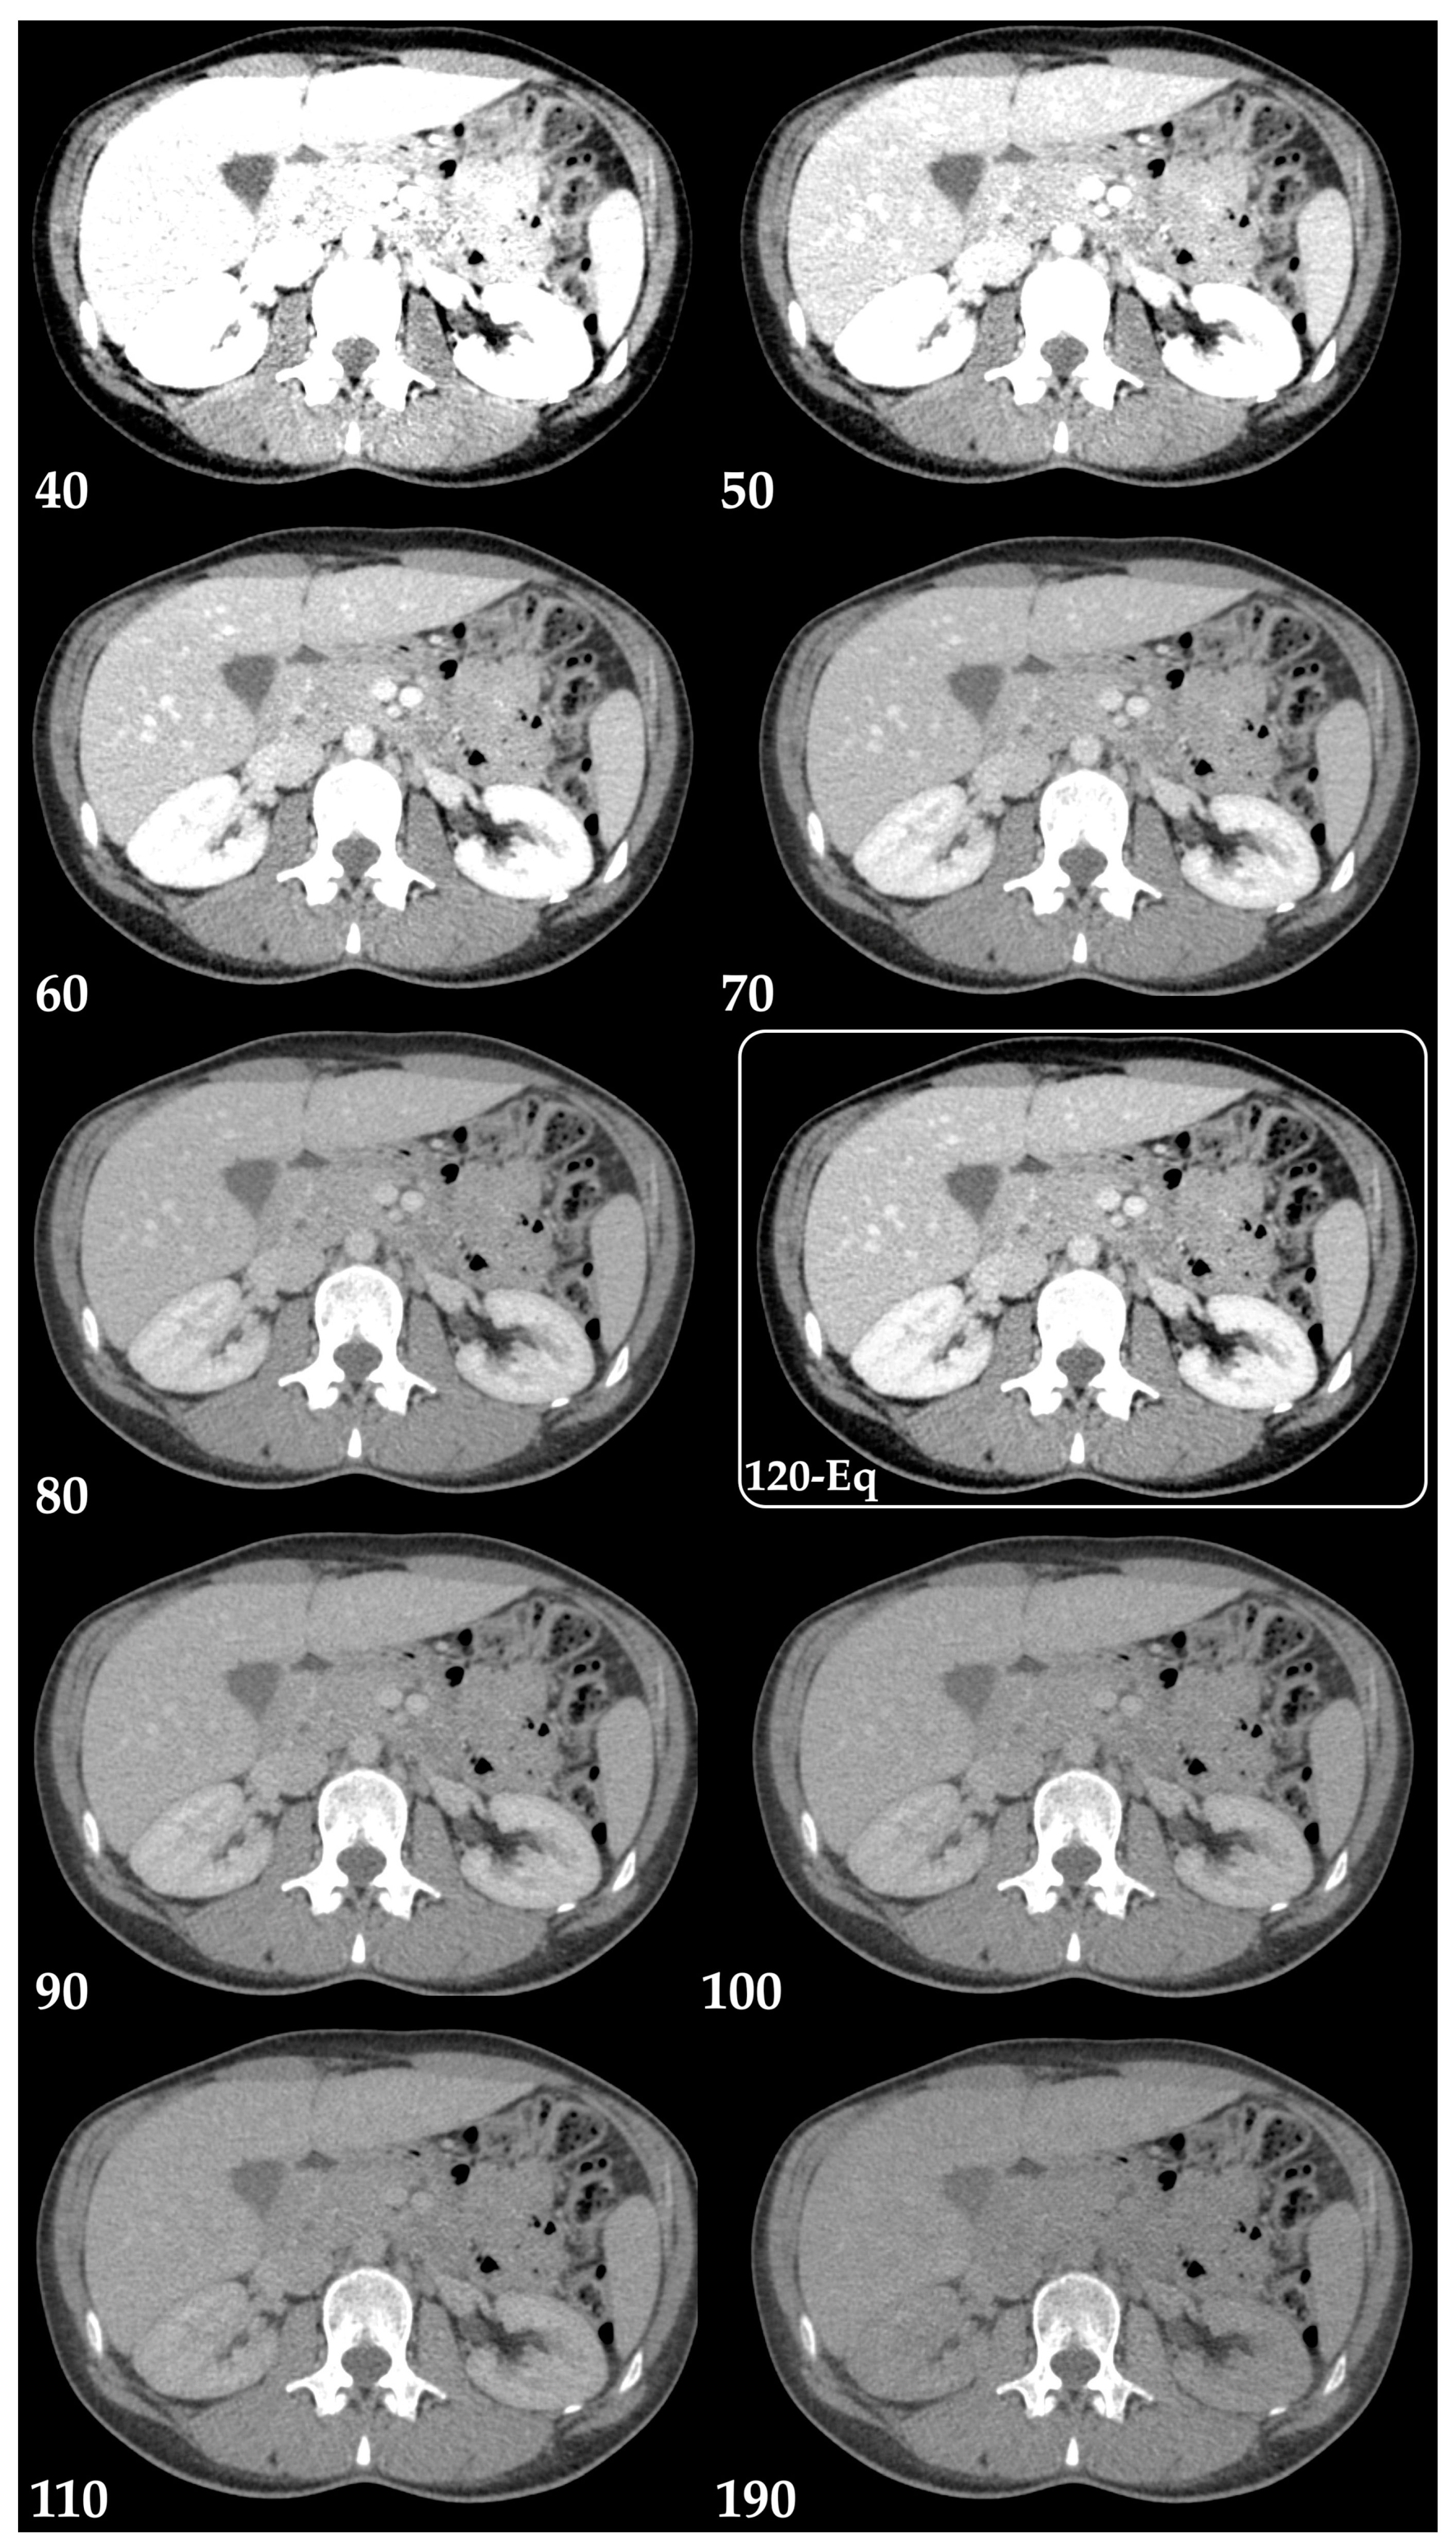

3.1. Postprocessing Techniques